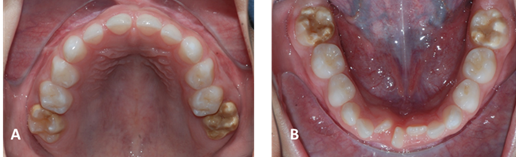

Al examen clínico intrabucal se observa relación molar clase III, con mordida cruzada posterior derecha, mordida borde a borde, presencia de diente supernumerario permanente en región incisiva inferior en giroversión (figura 1 ABC); piso de boca, paladar y encías sin lesión aparente. Unidades dentarias (UD) 1.6 y 2.6, con cambios morfológicos opacidades blancas y amarillo marrón a nivel tercio medio y cara oclusal de bordes difusos y fracturas post eruptivas en el esmalte, UD 3.6 y 4.6 con preparación cavitaria sin material restaurador en caras ocluso-lingual, realizadas en consulta privada hace dos meses aproximadamente y que se les desalojaron. (figura 2 AB). El paciente a las pruebas térmicas manifiesta sensibilidad al frio en UD 1.6, 2.6, 3.6 y 4.6. Se indica toma de modelos y estudio radiográfico.

Clínicamente en la HIM las lesiones abarcan desde opacidades demarcadas blanco amarillentas o amarillo amarronadas hasta severas hipomineralizaciones con ruptura del esmalte y con marcada sensibilidad a los cambios térmicos y pueden manifestar sintomatología dolorosa 3. En casos más severos se pueden observar fracturas posteruptivas de este esmalte más débil, debido a su mayor porosidad, lo que provoca disminución en sus propiedades mecánicas, tornándose quebradizo y pudiendo fracturarse con facilidad frente a fuerzas masticatorias normales 19. En este caso se observaron las lesiones de color amarillento marrón y el paciente manifestó sensibilidad al frio. Al igual que las fracturas posteruptivas referidas por la madre en la anamnesis. Con referencia a la prevalencia por sexo es mayor para el sexo masculino, situación coincidente con el caso, al igual que los dientes afectados por HIM que son en su mayoría molares, tal como se observa en el paciente con afectación en sus 4 primeros molares permanentes.

La HIM es un defecto de calidad, que se caracteriza por opacidades demarcadas de esmalte 9. Además, la pérdida de estructura del margen del tejido es rugosa e irregular, generalmente las lesiones se localizan en los dos tercios oclusales de la corona y disminuyen su severidad de oclusal a gingival 21. Este patrón de afectación se constató en el paciente ya en al margen gingival tenía ausencia de lesiones. Otro aspecto importante es que a mayor severidad de las lesiones a nivel molar aumenta la probabilidad de encontrar alguna manifestación en los incisivos 21. En el paciente estudiado se observaron lesiones que afectaron a todos los primeros molares permanentes, pero no se visualizaron en los incisivos centrales inferiores erupcionados y en sus controles, una vez erupcionados los incisivos superiores, no presentaron signos de HIM.